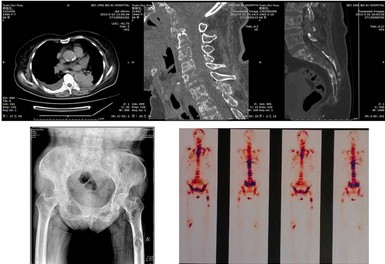

老年女性,因“颈背痛伴双上肢放射样疼痛8月,加重1月”住院。目前双上肢不同部位出现感觉减退,力量变化不大;尤其在坐位和站立时颈痛和双上肢疼痛加重;病史中还了解到近半年体重下降了20斤。入院后进行检查,颈椎CT提示多节段颈椎骨质破坏,颈5-6椎体压缩变性;颈椎MRI提示颈5-6变形的椎体压迫脊髓;肺CT发现左肺下叶占位性病变,纵膈心包转移,胸骨、肋骨破坏;腰椎CT提示T12椎体压缩骨折,骶骨破坏;骨扫描提示全身多发骨性转移(脊柱,骨盆,股骨,胸骨,肋骨);肿瘤标志物(AFP,CEA)显著提高;碱性磷酸酶高,尿本-周氏蛋白:阴性;甲状腺功能检查:正常;甲状腺抗体三项:正常;甲状旁腺激素测定:正常;血钙、磷:正常。综合分析初步诊断为:多发骨转移,肺癌可能大。